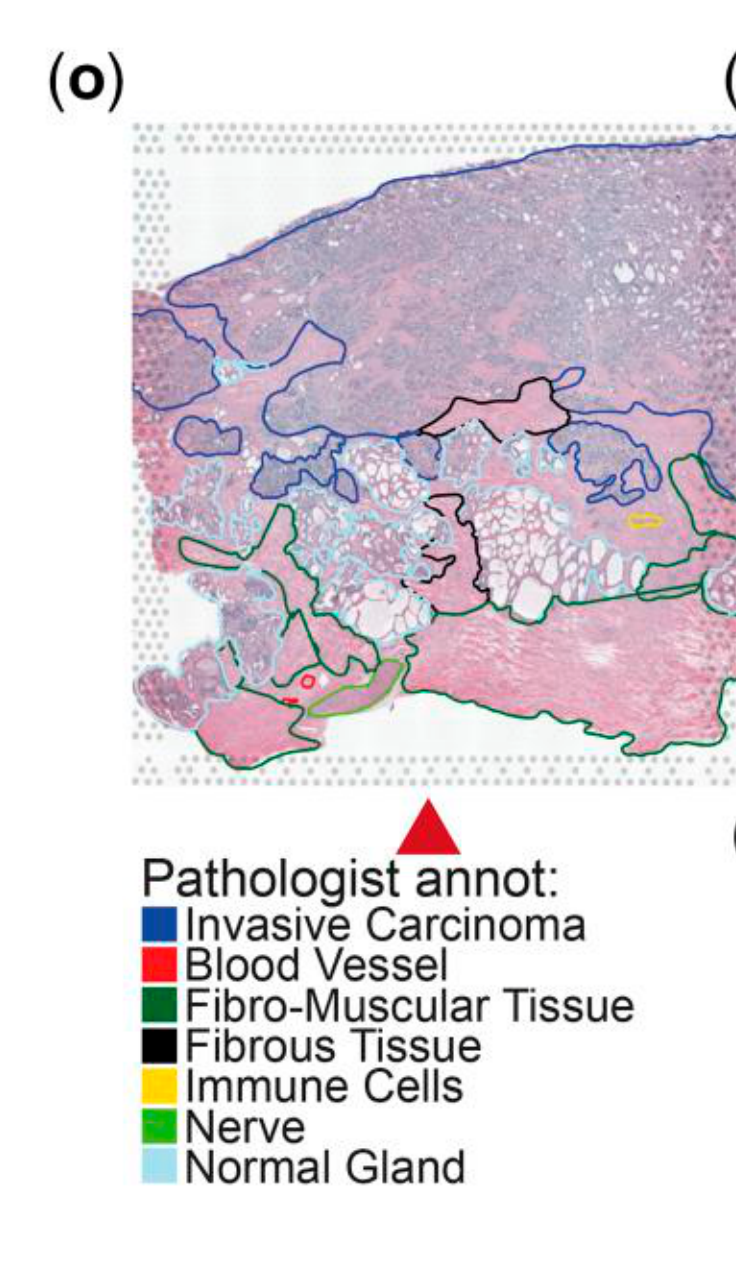

Jiang X. et al. - 2024

iIMPACT: integrating image and molecular profiles for spatial transcriptomics analysis

Condition Dimension

N/A

Data Components

Biological Annotation

Data

Metadata

None

Modality

Imaging-based

Resolution of observation

Multi-cellular

Visualized Elements

Observation

How are pathologist-defined tissue regions distributed across a cancer tissue section?

Biological

Tissue

Abstraction

Partial

Chart Type

Histological image

Communicative/Contextualization

Highlighting

Comparative Design

None

Layout

Spatial : Physical

Scalability Strategy

None (Item-level)